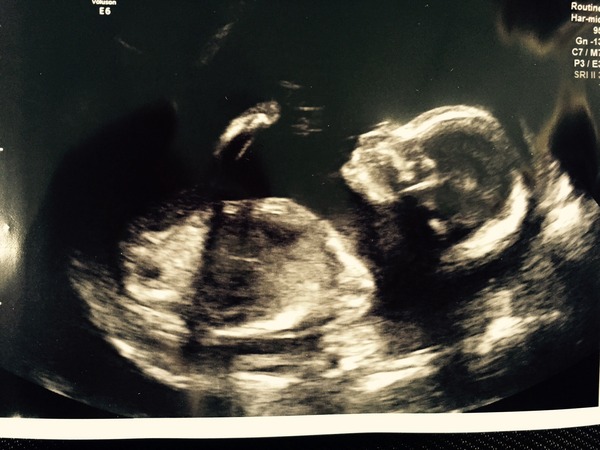

The scan pics are lovely!!

We are team blue and our scan was fine too. Here's a pic of the little man!